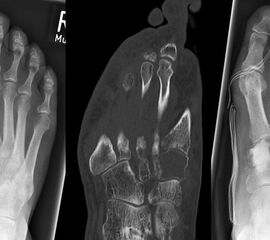

Die beiden häufigsten primären malignen Knochentumoren überhaupt, das Osteosarkom und Chondrosarkom, finden sich neben dem Ewing-Sarkom auch im Bereich des Fußes am häufigsten. Diese Tumoren können sich klinisch wie auch bildgebend sehr variabel darstellen, was die hohe Anzahl von Fehldiagnosen und verzögerten Diagnosestellungen erklären kann 25. Osteosarkome treten im Bereich des Fußes im Vergleich zu den typischen Lokalisationen (kniegelenksnah) durchschnittlich ca. 10 Jahre später auf (Abb. 15). Der Calcaneus ist die bevorzugte Lokalisation für Osteosarkome des Fußskeletts und ein Großteil dieser Tumoren ist schlecht differenziert (G3) 46. Das Verteilungsmuster des Ewing-Sarkoms ist noch heterogener. In einer Nachuntersuchung von 1997 zeigten sich 6 von 16 Ewing-Sarkomen im Bereich der Metatarsalia, 4 in den Phalangen, 3 im Calcaneus und jeweils eines im Talus und eines im Os navikulare 47. Das durchschnittliche Patientenalter unterscheidet sich nicht von den herkömmlichen Lokalisationen. Auffällig ist jedoch die erhebliche Diagnoseverzögerung. So vergehen bei einem Ewing-Sarkom-Befall des Fußes durchschnittlich 14 Monate von Beginn der Symptome bis zur korrekten Diagnosestellung, bei Lokalisation im Rückfuß sind es gar 22 Monate (Abb. 28). Die Therapie des Ewing- und Osteosarkoms des Fußes unterschei­det sich grundsätzlich nicht von der etablierten Behandlungsstrategie dieser Tumoren und umfasst in der Regel die neo-adjuvante Chemotherapie, weite Tumorresektion und anschließende adjuvante Chemotherapie. Die Strahlentherapie besitzt in der Behandlung des Ewing-Sarkoms unverändert einen hohen Stellenwert. Ewingsarkome sind definitions­gemäß stets schlecht differenziert (G3 bzw. G4), also hoch maligne. Das operative Vorgehen ist dieser Tatsache anzupassen.

Das Chondrosarkom des Fußes zeigt, ähnlich wie das Enchondrom, eine Prädilektion für die kurzen Röhrenknochen. Das durchschnittliche Alter liegt hier bei 52 Jahren mit einer Bevor­zugung des männlichen Geschlechts. In Abhängigkeit der Lokalisation und Graduierung des Tumors umfasst die geeignete operative Therapie die intraläsionale Curettage (G1) (Abb.19) bis hin zur Amputation (G3) (Abb.10) 34.